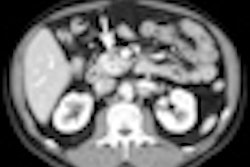

The treatment, which uses microsecond electrical pulses to force open and destroy tumor cells around blood vessels of the pancreas, was used to treat eight patients at the University of Miami Miller School of Medicine between December 2010 and September 2011. The patients received the interventional radiology treatment a median of nine months after being diagnosed. They also underwent two other methods of treatment to kill their cancerous tumors, which ranged from 2.5 to 6.8 cm in size.

Dr. Govindarajan Narayanan, chief of vascular and interventional radiology and associate professor of clinical radiology at the university, said that two of the patients were able to have surgery after the treatment; they had successful resections and remain cancer-free.